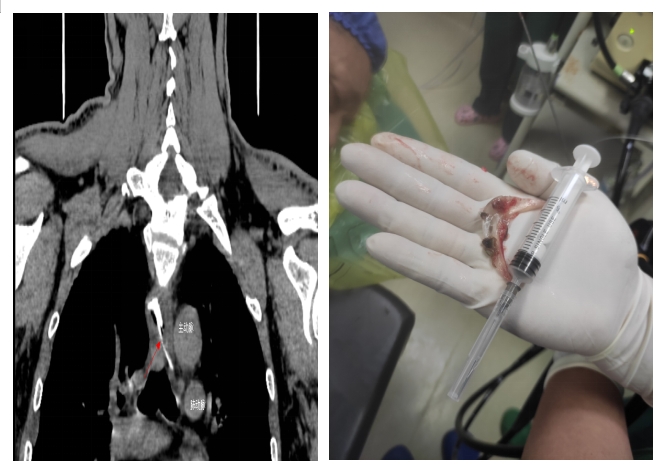

通訊員許欣報(bào)道:近日,衡陽市中心醫(yī)院心胸外科、消化內(nèi)科醫(yī)務(wù)人員在胃鏡下10分鐘取出刺穿食道的5×3厘米的魚頭骨,成功解除生命威脅。

當(dāng)日,黃先生在家中與家人聚餐時(shí),不小心被魚頭骨卡住,強(qiáng)行吞咽多次,出現(xiàn)食管與胸骨中上段后部疼痛,火速到衡陽市中心醫(yī)院就診。接診醫(yī)師對患者進(jìn)行評估,嘗試經(jīng)喉鏡治療時(shí),發(fā)現(xiàn)魚頭骨位置較深,行CT檢查發(fā)現(xiàn)魚頭骨卡于食管中段,穿破食管壁,與主動脈比鄰,非常危險(xiǎn),隨時(shí)威脅患者生命安全。隨即,患者被收治到心胸外科住院。入院后,廖金文主任一邊安慰,緩解患者的緊張情緒,一邊為其制定詳細(xì)的治療方案,計(jì)劃在手術(shù)室中嘗試胃鏡下取出魚刺。

在全身麻醉下,通過胃鏡,手術(shù)醫(yī)師清晰可見魚頭骨嵌頓部位為食管中上段。消化內(nèi)科副主任醫(yī)師劉昌智及主管護(hù)師羅雯娟攜手術(shù)室護(hù)理團(tuán)隊(duì),憑借豐富的臨床經(jīng)驗(yàn)與技術(shù),10分鐘內(nèi)為患者實(shí)施了胃鏡取異物治療,成功取出魚頭骨,黃先生轉(zhuǎn)危為安。為防止意外,手術(shù)期間,心胸外科醫(yī)師在手術(shù)室全程守護(hù)。